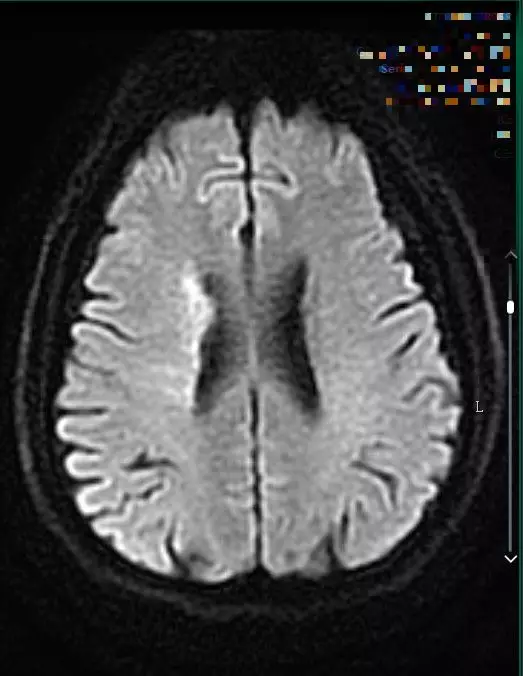

9:40分左右,患者逐渐开始出现烦躁、嗜睡,查体:言语不清,左侧肢体肌力0-1级,急查头颅MRI+MRA+颈部MRA阅片见,右侧基底节区急性脑梗死,右侧大脑中动脉闭塞。

头颅MRI+MRA(08-03日 11:50左右)